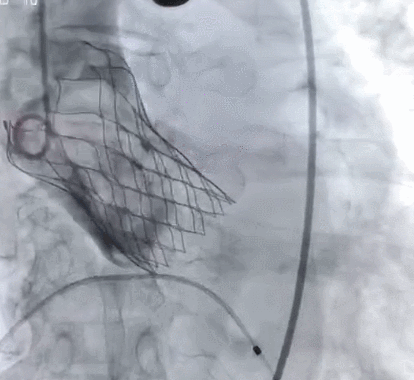

术后造影

主动脉CT检查诊断:三叶瓣,收缩期测得瓣环周长是81.6mm,左室流出道周长87.7mm(瓣下4mm),升主周长125mm(瓣上45mm);舒张期测得瓣环周长是82.2mm,左室流出道周长91.9mm(瓣下4mm),升主周长122mm(瓣上45mm)。最终决定植入TAV30瓣膜。

术后即刻:无瓣周漏,舒张压明显改善至68mmHg